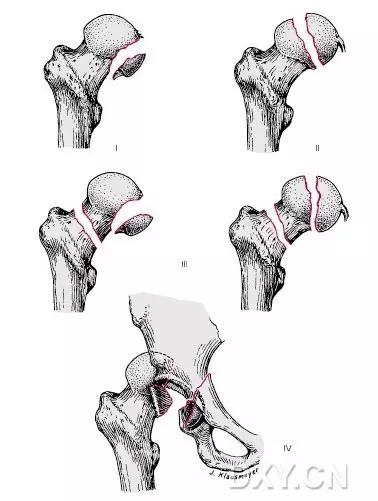

6. Pipkin 骨折

股骨头骨折。1957 年,Pipkin G 在文献中对其进行详细的描述并分型,至今仍在很多文献中被采用。

(来源:radiopaedia)

Ⅰ型:骨折块在圆韧带的下方;

Ⅱ型:骨折块在圆韧带的上方;

Ⅲ型:Ⅰ、Ⅱ两型任意一种伴股骨颈骨折;

Ⅳ型:Ⅰ、Ⅱ两型任意一种伴髋臼骨折 。